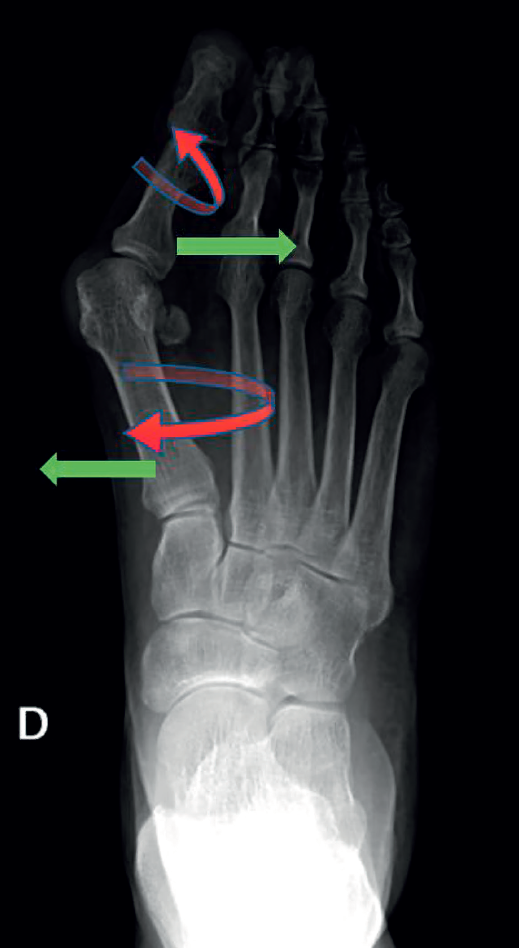

Consiste en una alteración de la articulación metatarsofalángica (MTF) del primer radio del pie. Es una deformidad compleja que incluye, por un lado, la desviación del primer dedo del pie (hallux o dedo gordo) hacia el resto del pie, alejándolo de la línea media del cuerpo (abducto), con una rotación en el plano frontal (pronación del primer dedo). Por otro lado, también incluye la desviación del primer metatarsiano (M1), aproximándolo a la línea media del cuerpo (varo de M1), con una pequeña rotación externa, como se puede ver en la Figura 1. Esta modificación de la articulación afecta a todas las estructuras anatómicas próximas, como la cápsula articular, los ligamentos colaterales, los huesos sesamoideos, la musculatura intrínseca y la extrínseca)(2).